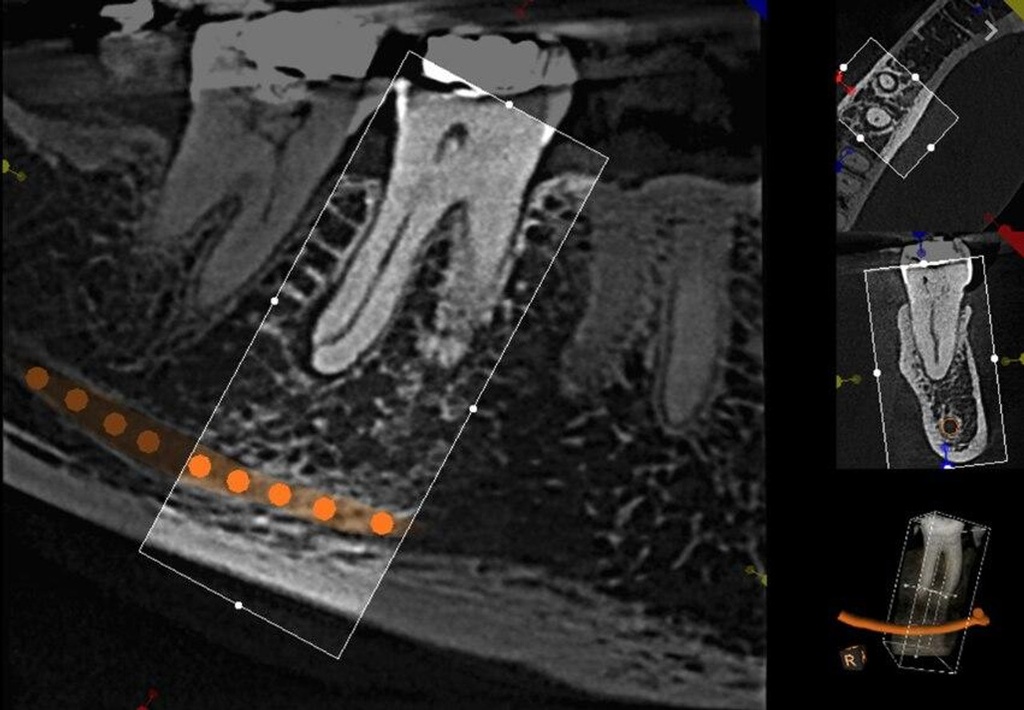

Introducing the CS 9300 Premium Panoramic, Cephalometric, and Cone Beam System from Carestream Dental – your ultimate solution for top-quality dental imaging. This state-of-the-art machine offers both 2D panoramic and cephalometric dental X-rays, as well as adjustable 3D cone beam images in up to seven different field of view sizes, extending up to 17x13.5 cm. This comprehensive range of imaging capabilities makes it a versatile tool, perfect for supporting a wide array of dental, surgical, or orthodontic examinations.

With the CS 9300 Premium, you can expect unparalleled image clarity and precision, allowing you to confidently diagnose and plan treatments with ease. Whether you're performing routine dental check-ups, complex surgical procedures, or orthodontic assessments, this system ensures outstanding results.

The CS 9300's 2D panoramic x-ray imaging capabilities are powered by variable focal trough technology, which provides optimal clarity for every image. The system's 3D imaging capabilities are based on cone beam technology, which delivers high-resolution images with a low radiation dose.

- Endodontics